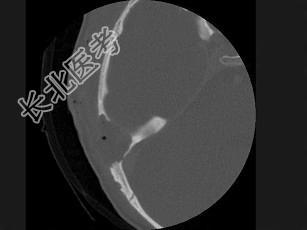

- 单项选择题女性,17岁, 右耳乳突区隐痛,右耳后乳突区出现包块, 逐渐增大,CT检查如图所示, 请选择最可能的 ( )